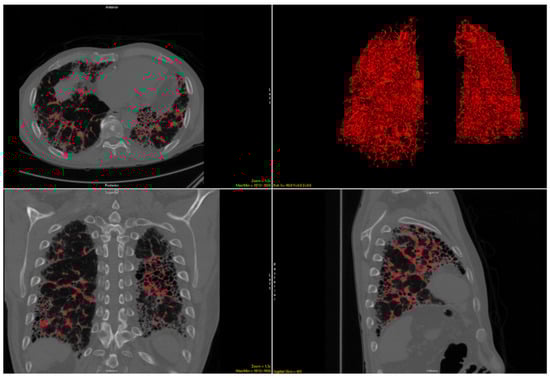

2.2. Imaging Analysis